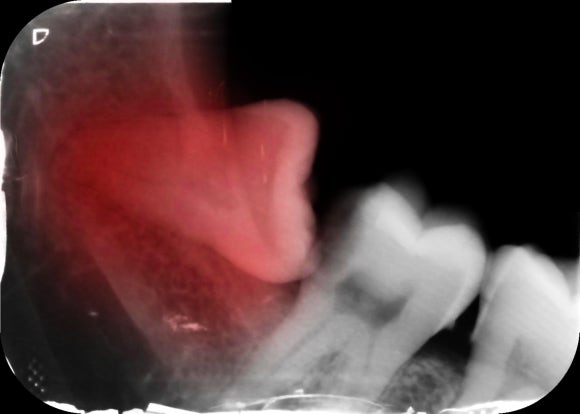

CT 촬영으로 신경관과 사랑니의 위치를 입체적으로 확인한 뒤

신경과 너무 가깝다면 즉시 발치 대신

경과 관찰이나 최소 절개 분할 발치 계획을 세우는 경우도 있어요.

신경관과 가까운 사랑니의 경우,

“대학병원 가야 하나요?”라는 걱정이 많습니다.

하지만 중요한 건 시술하는 환경과 진료자의 경험이에요.

CT로 신경관 위치를 정밀하게 분석한 뒤

분할 발치와 최소 절개로 진행하고 있어요.